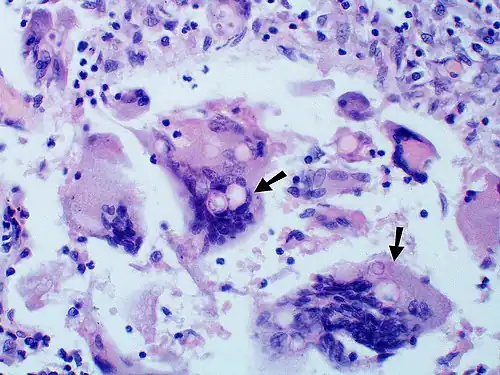

Large yeast-like fungi seen within giant cells at arrows. -

Large yeast-like fungi seen within giant cells at arrows. Budding yeasts in the cytoplasm of giant cells at the arrows. Broad-based budding and double-contoured cell walls are seen in the giant cell in the center are characteristic of Blastomyces dermatitidis. -